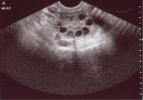

Curare la sindrome dell ovaio policisticoLa sindrome dell’ovaio policistico (Pcos) è tra le prime cause di sterilità femminile o di aborti spontanei durante i primi mesi di gravidanza e colpisce il 10-15% delle donne in età fertile

L’ovaio policistico provoca alterazioni nella produzione di alcuni ormoni, in particolare nella produzione di estrogeni e progesterone, i quali hanno il compito di aiutare le ovaie a liberare gli ovuli. In questo modo risulta molto difficile che le ovaie affette...